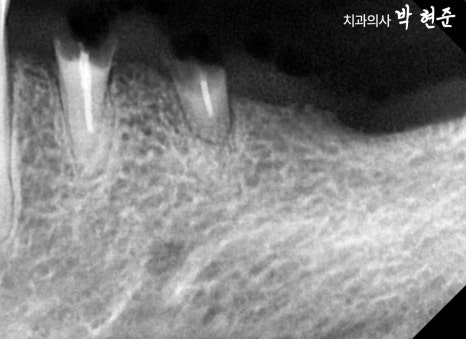

엑스레이 예시 사진을 관찰해보니

치관의 많은 양이 부러진 것으로 보여집니다.

이미 과거에 근관치료도 받았던 곳으로 보이기에

발치가 필요하겠습니다.